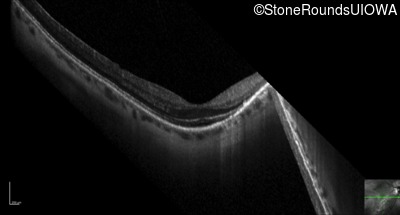

Optical Coherence Tomography - Right - 20/40 +2

Exemplar / OCT Stack